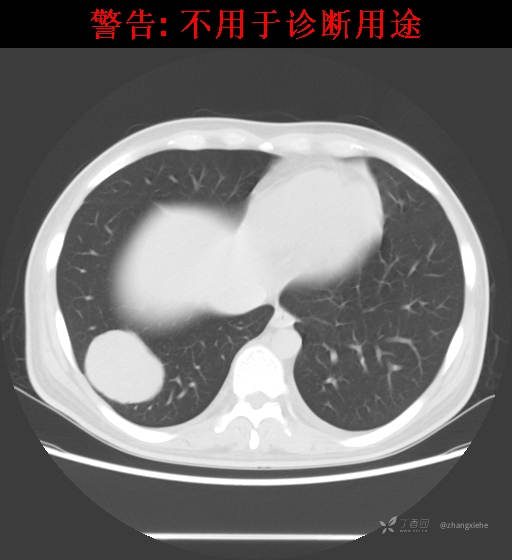

现病史:患者2022-02-07在市中医院体检发现右肺占位,胸部CT示:右肺下叶基底段见一不规则软组织密度影,增强扫描呈轻中度强化,可见血管贴边征。当时无任何不适。2022-02-24于省肿瘤医院行纤支镜检查阴性,痰检未找到癌细胞。经皮肺穿刺细胞学检查找到高度癌疑细胞,病理示:右下肺穿刺考虑神经内分泌癌。免疫组化结果:CgA(-)、CD56(-)、Syn(+)、CK广谱(-)、p40(-)、P63(少量+)、TTF-1(-)、Ki-67(+,40%)、NapsinA(-)、Calcitonin(-)、TG(-)。ECT示:全身骨扫描未见明确骨转移征象。患者出现贫血且逐渐加重、低蛋白血症,予人促红素注射液、精蛋白重组人胰岛素混合注射液、人血白蛋白对症处理,效果不明显,病情加重,右髋出现疼痛,不能行走。2022-03-04转院南大二附院进一步治疗,2022-03-20行右侧髂骨穿刺活检术,术后病理结果示:考虑软组织透明细胞肉瘤。免疫组化示:瘤细胞Vim(+)、NSE(+)、S-100(+)、SOX10弱(+)、Melan-A(+)、TFE-3部分弱(+)、CK(-)、MyoD1(-)、Desmin(-)、HMB45(-)、CD34(-)、CD68(-)、CR(-)、Ki-67约15%(+)。特殊染色示:网状纤维染色(-)、PAS(±)。

2022-03-05血常规示:血红蛋白:64g/L,生化示:白蛋白20g/L。骨髓涂片细胞学检查示:骨髓增生明显活跃,粒红比减低。粒、红、巨三系增生明显活跃。粒系伴成熟障碍。髓片浆细胞较易见,占7%。粒系增生明显活跃,核明显左移,可见巨幼样变及核浆发育不平衡。PET-CT示:1.右肺下叶软组织肿块、右侧耻骨下支及耻骨联合处骨质破坏伴软组织肿块形成,FDG代谢均异常增改,考虑恶性病变,建议病理检查;右侧髂血管旁、双侧腹股沟淋巴结反应性增生,建议随访。2.多浆膜腔(双侧胸腔、心包腔、盆腔)少量积液。3.全身骨骼FDG代谢弥漫增高,考虑骨髓反应性增生。4.大小肠条片状FDG代谢增高,考虑生理性摄取。5.右侧上颌窦面膜下囊肿,脑部FDG代谢未见明显异常。6.C7-T1层面后纵韧带钙化。患者乏力加重,卧床不起,不能承重,大小便不顺畅,转院至我院。门诊拟“1.右肺占位并右侧骨盆转移2.低蛋白血症3.中度贫血 4,血糖升高(原因待查)”收入住院。患者发病以来,无胸闷、胸痛,无呼吸困难,偶咳嗽,无咳血,饮食、睡眠欠佳,2个月之内体重减轻约10kg。